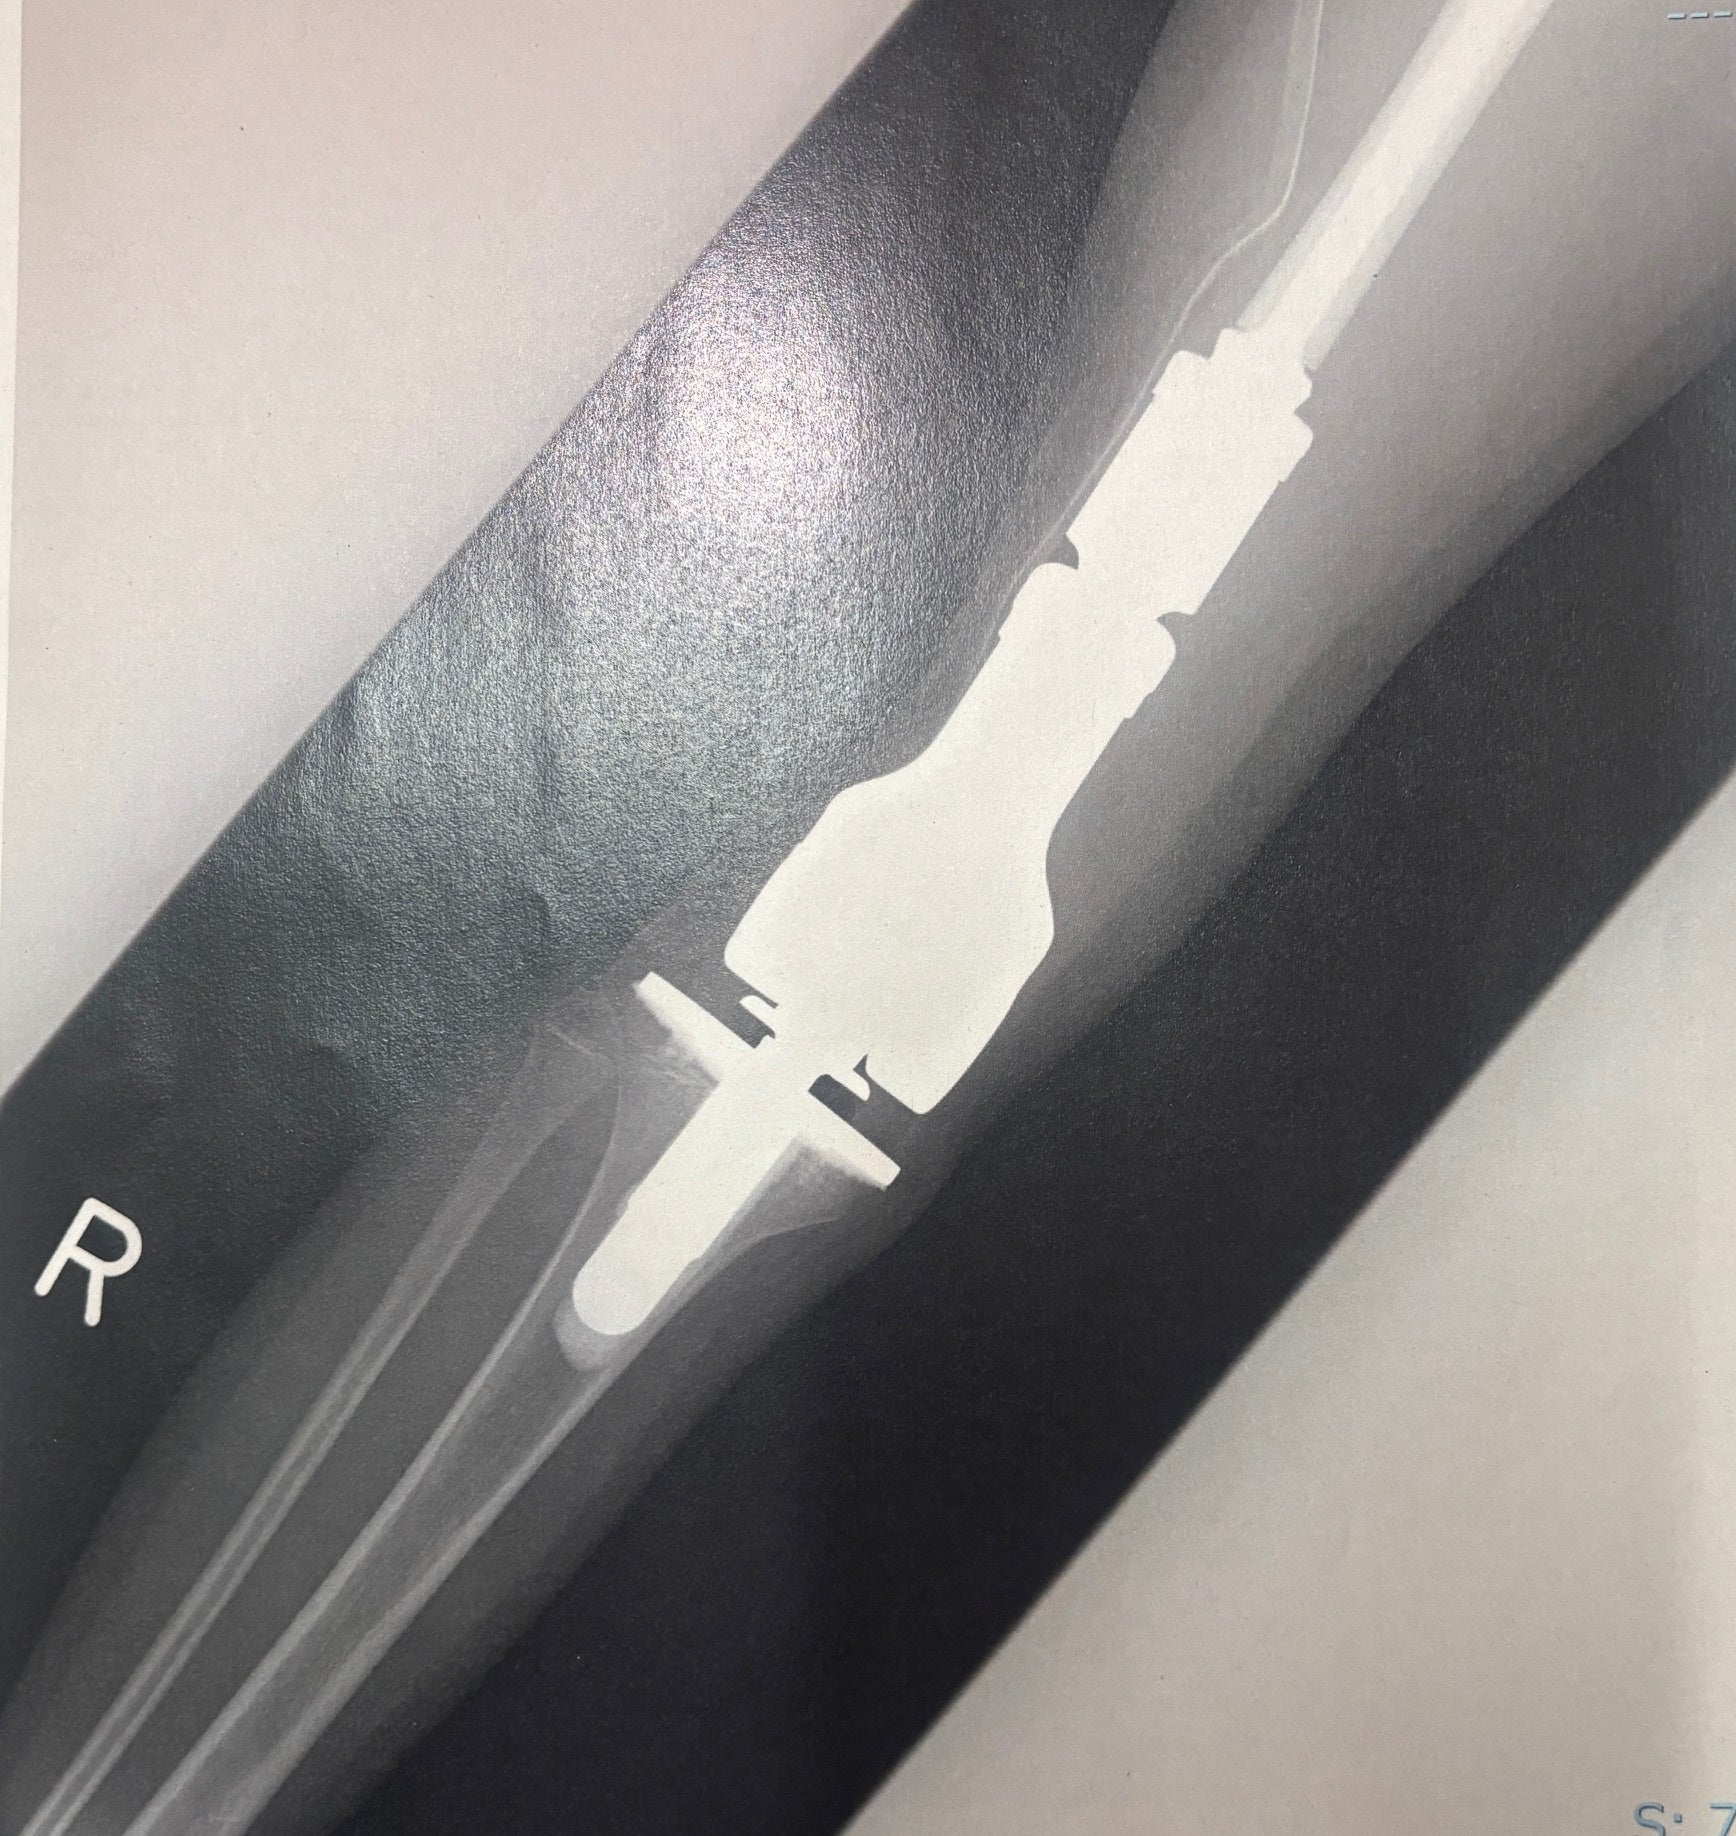

実際の人工関節のレントゲンまた、人工関節は体の内部の器具ですから、外見(例えば服を着たりしている)からは全くわかりません。ですので、火事が起こったり、地震などの災害が起こったりした場合、走ったり、しゃがんだり、迅速に動く事ができない事もあります

しかし、次女の腫瘍での人工関節とスポーツ等で膝を痛めての人工関節は大きく違います

A:関節の表面だけを削って人工物に置き換える通常の人工関節に比べて、腫瘍用人工関節は、広範囲に切除した悪い腫瘍部分を補わなければならないことが一般的であるために、より大きなものになります。

多くの骨と筋肉を切除するのが腫瘍用人工関節の為、より日常に戻る事、走る事、運動する事が難しいとされております